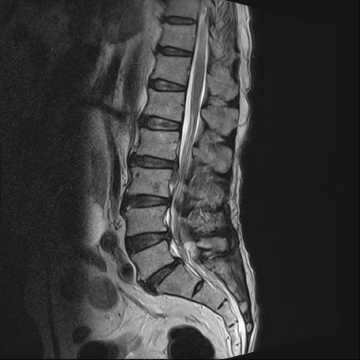

허리 디스크 수술 전·후

2021.10.19

2023.01.09

ㆍ환자 동의를 받은 자료이며, 이미지 사진은 실물과 다를 수 있습니다.

ㆍ모든 자료는 새움병원 자료입니다.